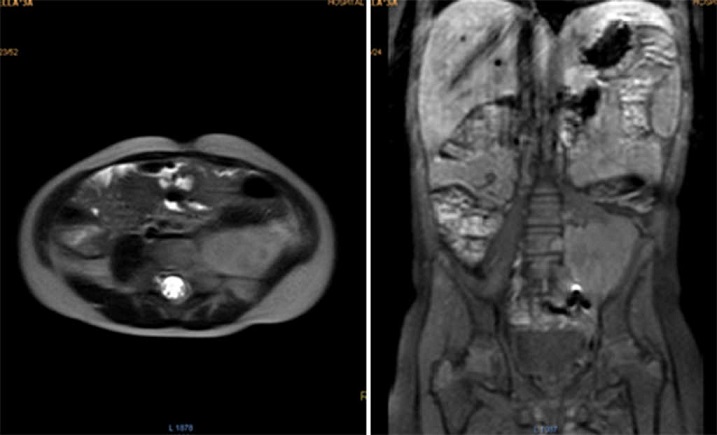

Durante los controles por oncología, los exámenes de laboratorio han sido normales. La RMN de abdomen tomada en el postoperatorio reportó una masa residual de 42.2 x 53.6 mm (Fig. 3). Tres meses después una ecografía mostró un aparente aumento del tamaño tumoral, de 73 x 54 x 58 mm. Posteriormente fue discutida en la junta de oncología pediátrica, y se decidió iniciar quimioterapia con ciclos de ifosfamida más doxorubicina, alternados con ifosfamida más etopósido.

Figura 3 Resonancia magnética de abdomen con contraste mostrando a nivel paravertebral izquierdo masa de bordes definidos de aspecto heterogéneo en todas las secuencias, que mide aproximadamente 42.2×53.6mm, con ávido realce de la lesión con el medio de contraste.